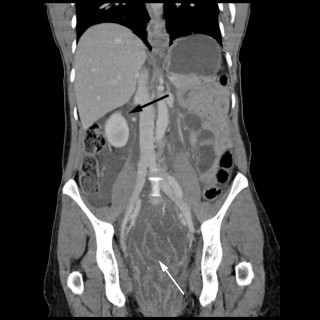

Magesmerter hos barn er en hyppig årsak til henvisning til barnemedisinsk og kirurgisk spesialisthelsetjeneste. Akutt appendisitt, obstipasjon og gastroøsofageal refluks er blant de vanligste diagnosene. Ofte kan barn ha diffuse symptomer, og selv om «det vanligste er det vanligste», er det viktig å være oppmerksom på symptomer som tyder på alvorlig, underliggende patologi. Tett samarbeid mellom fastlege, barnelege, barnekirurg og radiolog kan være viktig for å komme til målet. En jente tidlig i tenårene hadde vært plaget av «treg mage» siden småbarnsalder og hadde gjennom de siste fem årene...